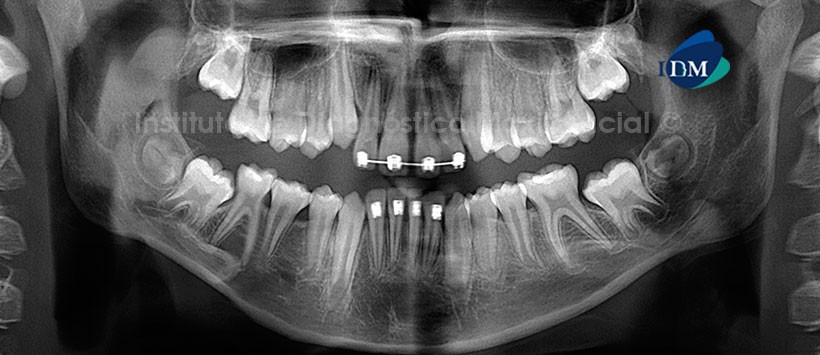

Paciente masculino d 10 años de edad, acude al Instituto de Diagnostico maxilofacial por evaluación general.

A la evaluación de la radiografía panorámica (Figura 1), se aprecia aparatología fija para ortodoncia en sector dentario anterior, las segundas molares en proceso de erupción y los gérmenes dentarios de las terceras molares en evolución intraósea, teniendo en consideración que los gérmenes de las piezas 18 y 28 presentan una anomalía dentaria respecto al tamaño (microdiente).

A la evaluación tomográfica, se pudo confirmar la presencia de estos microdientes (Figura 2). Sin embargo en la reconstrucción multiplanar (vista axial, coronal y sagital) se pudo observar la presencia de diente supernumerario localizada a nivel del paladar (próximo a la sutura intermaxilar) (Figura 3). En los cortes transaxiales y tangenciales se pudo localizar de manera exacta a los folículos de las piezas 18 y 28, las cuales están localizadas próxima a la tabla ósea vestibular (Figura 4).

La reconstrucción 3D, brinda de manera ilustrativa la ubicación de etas piezas anómalas así como su morfología y relación con estructuras Oseas y/o dentarias adyacentes.

Conclusión: Diente supernumerario y microdientes